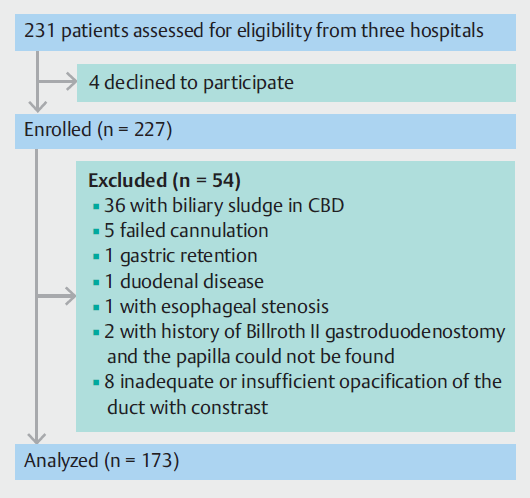

在2020年9月1日至2021年6月15日期间,共从三家医院招募了231名CBD结石患者。其中,173人符合纳入标准。共有58名患者被排除在外,原因如(图3)所示。患者队列的特征如(表1)所示。总共有46名评分为0或1的患者被计算机辅助设计系统归类为困难组,127名评分为2或以上的患者被归类为容易组。图1显示了两组的四个典型图像。

图3. 研究流程图。